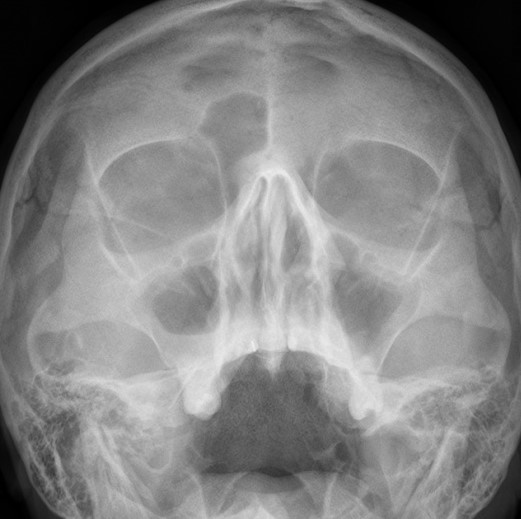

После операции:

— контрольный снимок (раньше делали ОПТГ, сейчас — строго КЛКТ)

Признаюсь, не совсем понимаю необходимости назначения консультации ЛОР-врача всем пациентам поголовно. Скажем, если у пациента нет жалоб со стороны носовой полости, нет вазомоторного или аллергического ринита, на КЛКТ все носовые пазухи воздушные и чистые, их сообщение с носовой полостью не нарушено — каков смысл гонять пациента к ринологу?